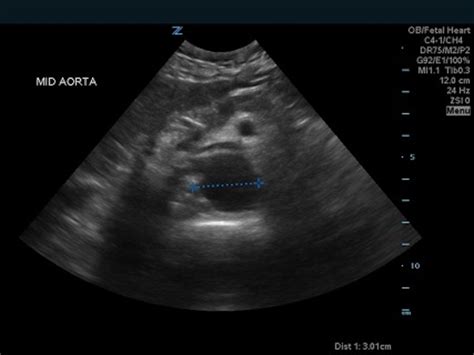

Ultrasound Non-invasive and excellent for initial screening.

Once an Iliac Artery Aneurysm is diagnosed, the treatment plan is usually dictated by the size of the aneurysm and the patient’s overall health. Small, stable aneurysms are often managed through "watchful waiting"—regular ultrasound or CT imaging to monitor for growth.

• iliac artery aneurysm radiology